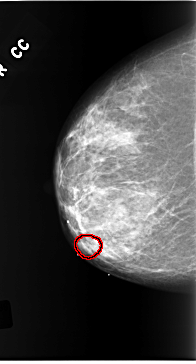

C_0168_1.RIGHT_CC

RIGHT_CC LINES 5816 PIXELS_PER_LINE 3136 BITS_PER_PIXEL 12 RESOLUTION 50 OVERLAY

FILE: C_0168_1.RIGHT_CC.OVERLAY

TOTAL_ABNORMALITIES 1

ABNORMALITY 1

LESION_TYPE MASS SHAPE OVAL MARGINS OBSCURED

ASSESSMENT 4

SUBTLETY 2

PATHOLOGY MALIGNANT

TOTAL_OUTLINES 1

BOUNDARY